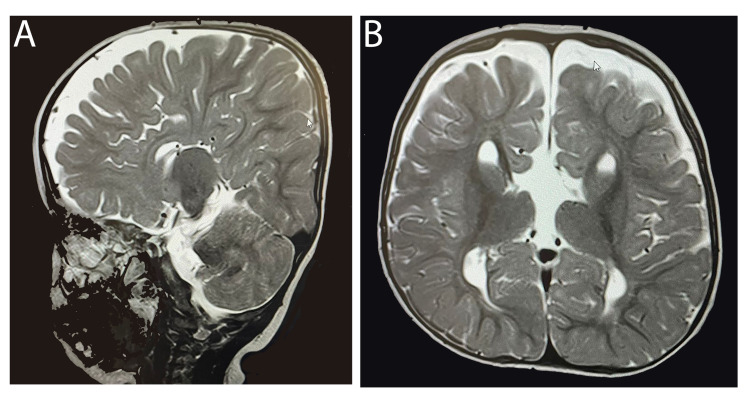

患者被 CI 委員會確定為雙側(cè)植入的候選者。 在三歲零五個月大時,進行了雙側(cè)同時人工耳蝸植入(HiRes™ Ultra #D 人工耳蝸,右 HiFocus™ SlimJ 電極和左 HiFocus™ Mid-Scala 電極,Advanced Bionics AG,加利福尼亞州,美國)。 術(shù)后 X 線顯示 CI 陣列有效插入耳蝸內(nèi)(圖 2)。 手術(shù)后第二天開機,并給予兩個 Naida CI Q70 聲音處理器(Advanced Bionics AG,加利福尼亞州,美國)。

An external file that holds a picture, illustration, etc.

Object name is cureus-0014-00000021063-i02.jpg

病例 2 的術(shù)后 X 線顳骨顯示雙耳人工耳蝸電極陣列有效插入